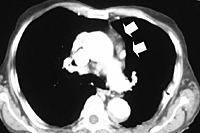

Subsequently, all mediastinal fat that is found in the pretracheal space, along the internal mammary pedicles, in the aorto-pulmonary window (Figure 7), as well as in the right (Figure 8) or left (Figure 9) pericardiophrenic angles that may contain ectopic thymic tissue is completely excised to accomplish an extended thymectomy (Figure 10).

In a recent series of 31 patients we had only one patient who required conversion to median sternotomy [4]. Mean operative time averaged 148 minutes, although in the last 10 patients it averaged 100 minutes. At pathologic examination ectopic thymic tissue was found in 10 patients (32%). It was located within the anterior mediastinal fat in 5 patients, in the aorto-pulmonary window in 3, and in the pretracheal or cardiophrenic fat in 2 patients each. Two patients had ectopic thymic tissue in two distinct locations. There was no operative death. One patient sustained a myasthenic crisis that required reintubation and mechanical ventilation for few days. Mean hospital stay was 5.2 days.